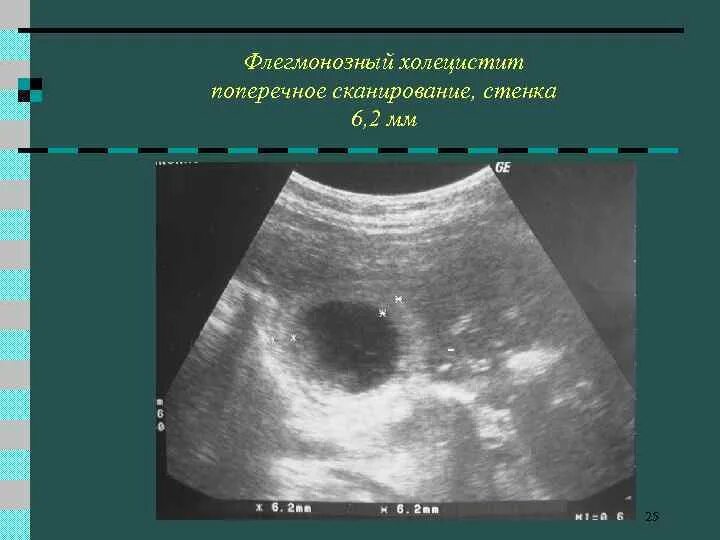

Липоматоз изменение поджелудочной железы